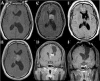

Purpose: Central neurocytoma is a rare intraventricular brain tumor that affects young adults and presents with increased intracranial pressure secondary to obstructive hydrocephalus. Typically, it has a favorable prognosis after adequate surgical intervention, but in some cases the clinical course is more aggressive. In this report, we describe the diagnosis and treatment of central neurocytoma in a series of patients at our institution.

Patients and methods: Our series of nine patients (M:F=2:7, mean age, 28.2 years) with ventricular tumors showed typical radiological, histologic and immunohistochemical features of central neurocytoma. Most patients received craniotomy with removal of the tumor through transcallosal or transcortical approach. The surgical and histopathologic data of these patients were reviewed and analyzed.

Results: The prognosis is generally favorable. Although most patients were alive and well at the last follow-up, two developed recurrence. Typical histologic features of recurrent neurocytoma include high proliferative activity (MIB-1 labeling index: 2.0-6.8%), prominent vascular proliferation and remarkable synaptophysin expression. Two patients (non-recurrent) died during follow-up due to sepsis or central failure. The MIB-1 labeling indices were as high as 2.2-5.4% for these two patients.

Conclusion: Although central neurocytoma is generally a benign neoplasm, some variant forms of recurrence are also present. Complete resection provides favorable long-term prognosis in most cases. Recurrent tumors are often local and the patients seem to recover well after a second resection followed by radiotherapy. Histologic features such as tumor proliferation (MIB-1 labeling index), vascular proliferation, and synaptophysin expression are often prominent in the recurrent tumor. We recommend that these histologic features be considered for tumor recurrence during treatment and follow-up of these patients.